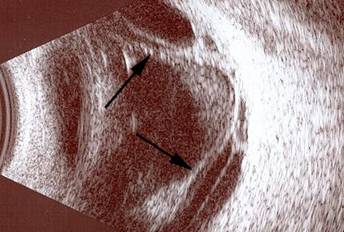

Bazı durumlarda retina, normal fundus muayenesi ile net seçilemeyebilir. Bu gibi durumlarda, göz ultrasonografisi çekilir.

Resim 8: Normal göz ultrasonografi görüntüsü. Beyaz ok göz sıvısını (vitreus), siyah ok retina tabakasını göstermektedir.

Resim 9: Yandaki resimde traksiyonel retina dekolmanı olan bir hastanın göz ultrasonografisi görülmektedir. Retinanın normal yerinden öne, göz sıvısı içine doğru çekildiği izlenmektedir (siyah oklar).